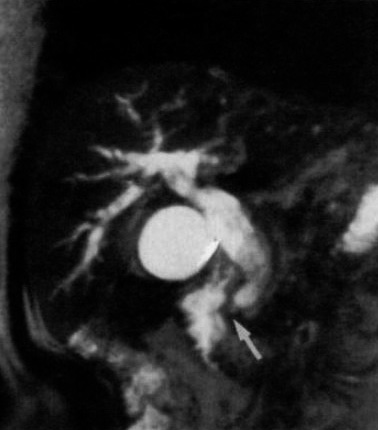

図10. Vater乳頭部癌による総胆管閉塞.胆管拡張,閉塞部の性状がMRCPで明瞭に描出されている.

【要旨】高度T2強調グラディエントエコー法であるCE-FAST法による胆道系の撮像を試みた.TR/TE 17/7msec,フリップ角70°,192×256マトリックス,スライス厚5mmの2D冠状断,矢状断像を,12秒息止め下にシーケンシャルに撮像し,これをMIP法で再構成して表示した.健常ボランティア5名,閉塞性黄疸症例13名を撮像し,健常者ではUS所見,患者ではCT, PTC, MRCP所見などと比較検討した.

健常者では5名中2名で撮像に成功したが,肝内胆管は描出できなかった.閉塞性黄疸患者では13名中11名で成功し,いずれも閉塞性高位が明らかとなり,一部の症例で閉塞原因を診断することができた(図10).

元画像は冠状断が適当で,矢状断は不要であった.不成功例の原因は,空間分解能の不足,心拍などの動き,胆汁のフローボイドなどが考えられる.MR胆道撮像法は,非侵襲的な胆道検査法として有用であるが,なお技術的改良が必要である.

【解説】MRCPの初報である.提示されている画像の画質はまだ不十分であるが,胆道,膵管を直接描出する画像診断法として,PTC,ERCPにかわる全く無侵襲な方法を提案した点で画期的な論文である.ここでは2Dグラディエントエコー法を使用しているが,この翌年1992年に日本の森本らが3D法を試み[33],さらに1994年には竹原らが高速スピンエコー法を使用した改良法を提案し[34],その後もMRCPの画質改良が進み,臨床検査として急速にその地位を確立した.